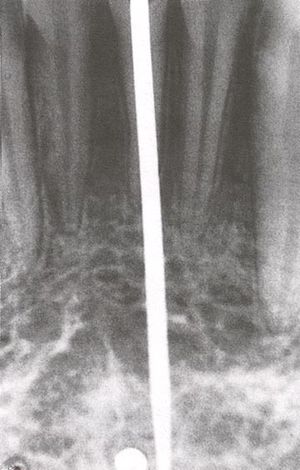

While studying bone cells in a rabbit femur using a titanium chamber, Branemark was unable to remove it from bone. His realization that bone would adhere to titanium led to the concept of osseointegration and the development of modern dental implants. The original xray of the chamber embedded in the rabbit femur is shown (made available by Branemark).

In the 1950s research was being conducted at Cambridge University in England to study blood flow in vivo. These workers devised a method of constructing a chamber of titanium which was then embedded into the soft tissue of the ears of rabbits. In 1952 the Swedish orthopaedic surgeon, Per-Ingvar Brånemark, was interested in studying bone healing and regeneration. During his research time at Lund University he adopted the Cambridge designed "rabbit ear chamber" for use in the rabbit femur. Following the study, he attempted to retrieve these expensive chambers from the rabbits and found that he was unable to remove them. Brånemark observed that bone had grown into such close proximity with the titanium that it effectively adhered to the metal. Brånemark carried out further studies into this phenomenon, using both animal and human subjects, which all confirmed this unique property of titanium.

Although Brånemark had originally considered that the first work should centre on knee and hip surgery, he finally decided that the mouth was more accessible for continued clinical observations and the high rate of edentulism in the general population offered more subjects for widespread study. He termed the clinically observed adherence of bone with titanium as "osseointegration". In 1965 Brånemark, who was by then the Professor of Anatomy at Gothenburg University in Sweden, placed his first titanium dental implant into a human volunteer.[5](p. 626)